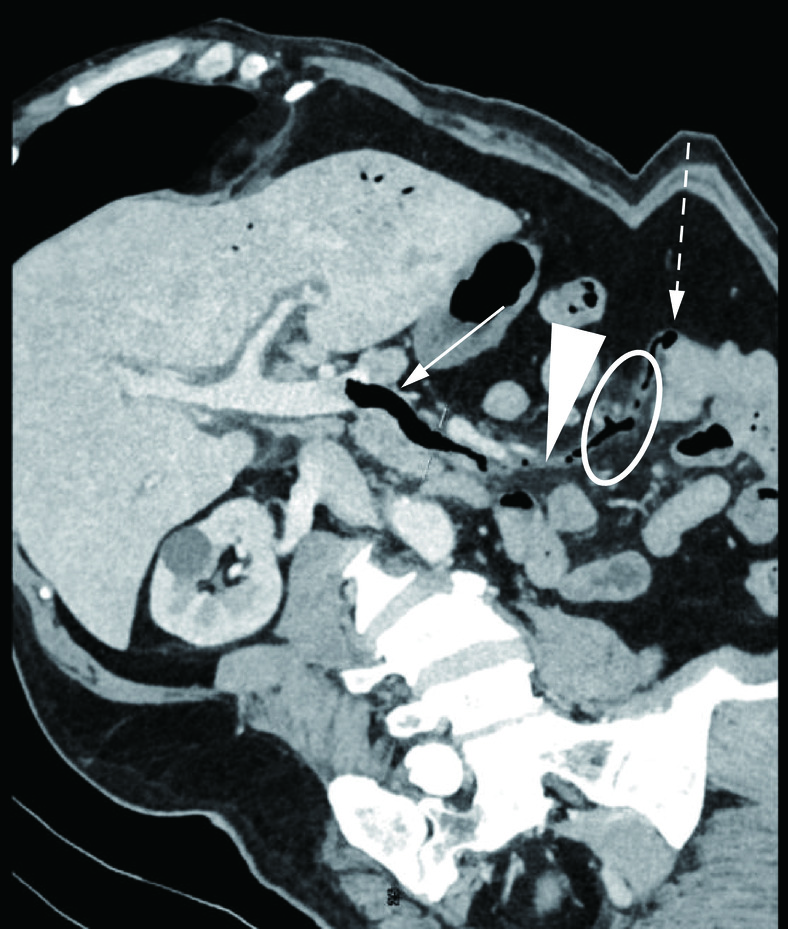

1.2.2 腹部MSCT所见

MSCT所见:肝门静脉主干、肝内门静脉分支及肠系膜上静脉内可见点状及条状气体密度影,门静脉期增强扫描肠系膜上静脉内气体旁可见条形低密度充盈缺损(图1)。空肠近段管壁见多发囊袋样突出憩室影,部分憩室周围脂肪间隙可见渗出影,并通过多方位重组(multiplanar reconstruction,MPR)发现其中一憩室穿孔,且憩室破口与邻近的肠系膜上静脉相通(图2)。通过曲面重组(curved planar reformation,CPR)可清晰显示空肠憩室破口与邻近积气的肝门静脉分支关系及肠系膜上静脉血栓情况(图3)。胆囊壁增厚,胆囊窝及肝门区可见少量积液。MSCT诊断:空肠近段多发憩室,空肠憩室穿孔伴肝门静脉、肠系膜上静脉血。

回顾本病例,患者以无明显诱因发热、持续性腹痛入院,我们分析患者出现发热腹痛的原因可能是空肠憩室破口与肠系膜静脉相通后,导致肠系膜上静脉内血栓形成,造成肠系膜上静脉发生炎症反应,进而进展为肠系膜上静脉周围腹膜炎所致。CPR重建图像(图3)显示肠系膜上静脉周围脂肪间隙浑浊,符合腹膜炎改变,也印证了我们的推测。MSCT可见空肠憩室穿孔并肝门静脉积气、肠系膜上静脉血栓,与术中所见及病理诊断相符。MSCT通过MPR多角度重建技术能清晰显示空肠憩室穿孔并与肠系膜上静脉相通的确切位置,通过MSCT血管追踪重建技术可准确显示肝门静脉积气与空肠憩室关系,从而找到了了肝门静脉内积气的病因,为临床诊治提供了重要信息。增强MSCT通过MPR重建及血管追踪重建技术的应用确切显示了肠系膜上静脉内存在血栓的情况,这与手术中所见及病理相吻合。日后工作中如再遇到类似病例,我们计划对患者进行CT小肠造影(CTE)检查,CTE作为一种无创性检查手段,可以同时观察肠内、外病变的情况[15],有助于清晰显示空肠憩室。